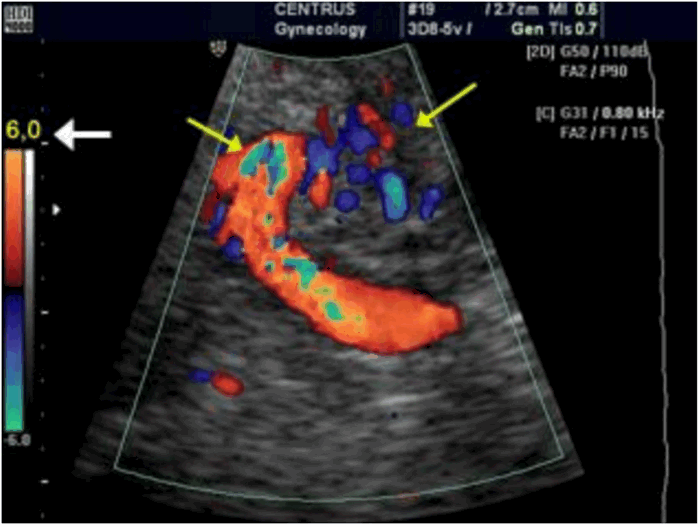

Рисунок 4: Искажения цветного доплеровского изображения и цветовые артефакты. На цветном изображении присутствуют области с искажениями кровотока (отмечены желтыми стрелками).

Рисунок 5: Снижение усиления по цвету и повышение частоты повторения импульсов.